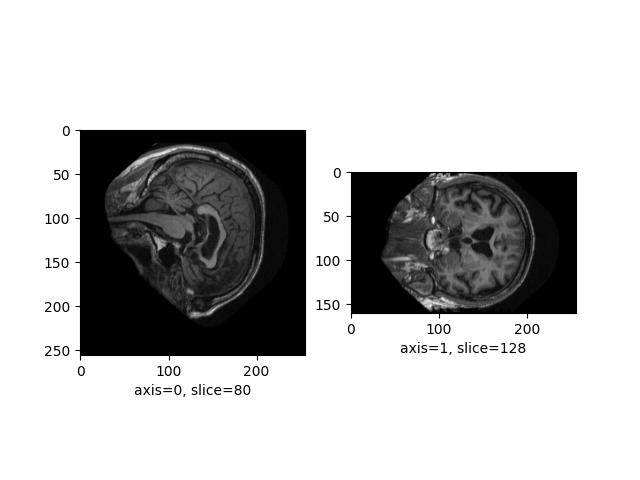

Plot the raw image¶

Let’s plot the sagittal and coronal axes of the image:

from neuroplot.plot.single import SinglePlot

plotter = SinglePlot(axes=[0, 1])

plotter.plot(img_path=image_path)

<Figure size 640x480 with 2 Axes>